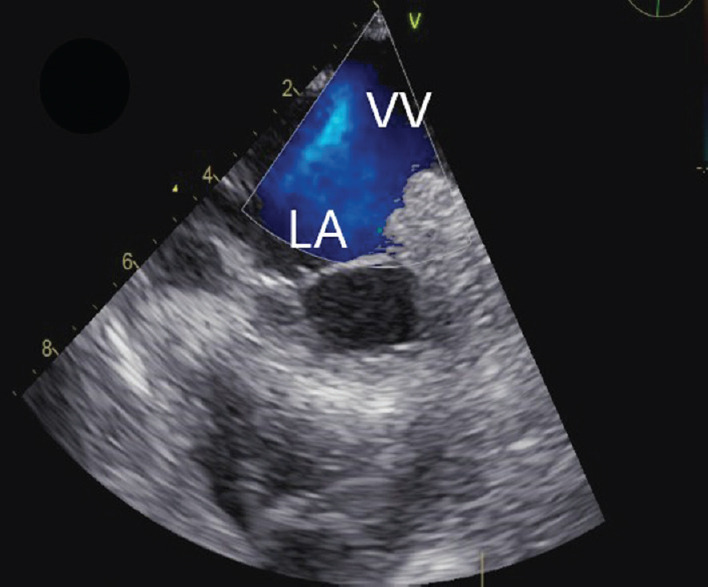

全肺静脉连接异常(TAPVC)是一种罕见的紫绀型先天性心脏病,成年后存活的患者更是少之又少。在此,我们介绍了一例 26 岁女性的病例,她在怀孕期间偶然被诊断出患有心上型 TAPVC。所有四条肺静脉汇合成一条共同的静脉汇流口,排入一条左侧垂直静脉,该静脉排入腹股沟静脉。

Total anomalous pulmonary venous connection (TAPVC) is a rare cyanotic congenital heart disease and their survival into adulthood is even rarer. Here, we present the case of a 26-year-old female who was incidentally diagnosed with a case of supracardiac TAPVC during her pregnancy. All four pulmonary veins were joining to form a common venous confluence which drained into a left-sided vertical vein which drained into the innominate vein.